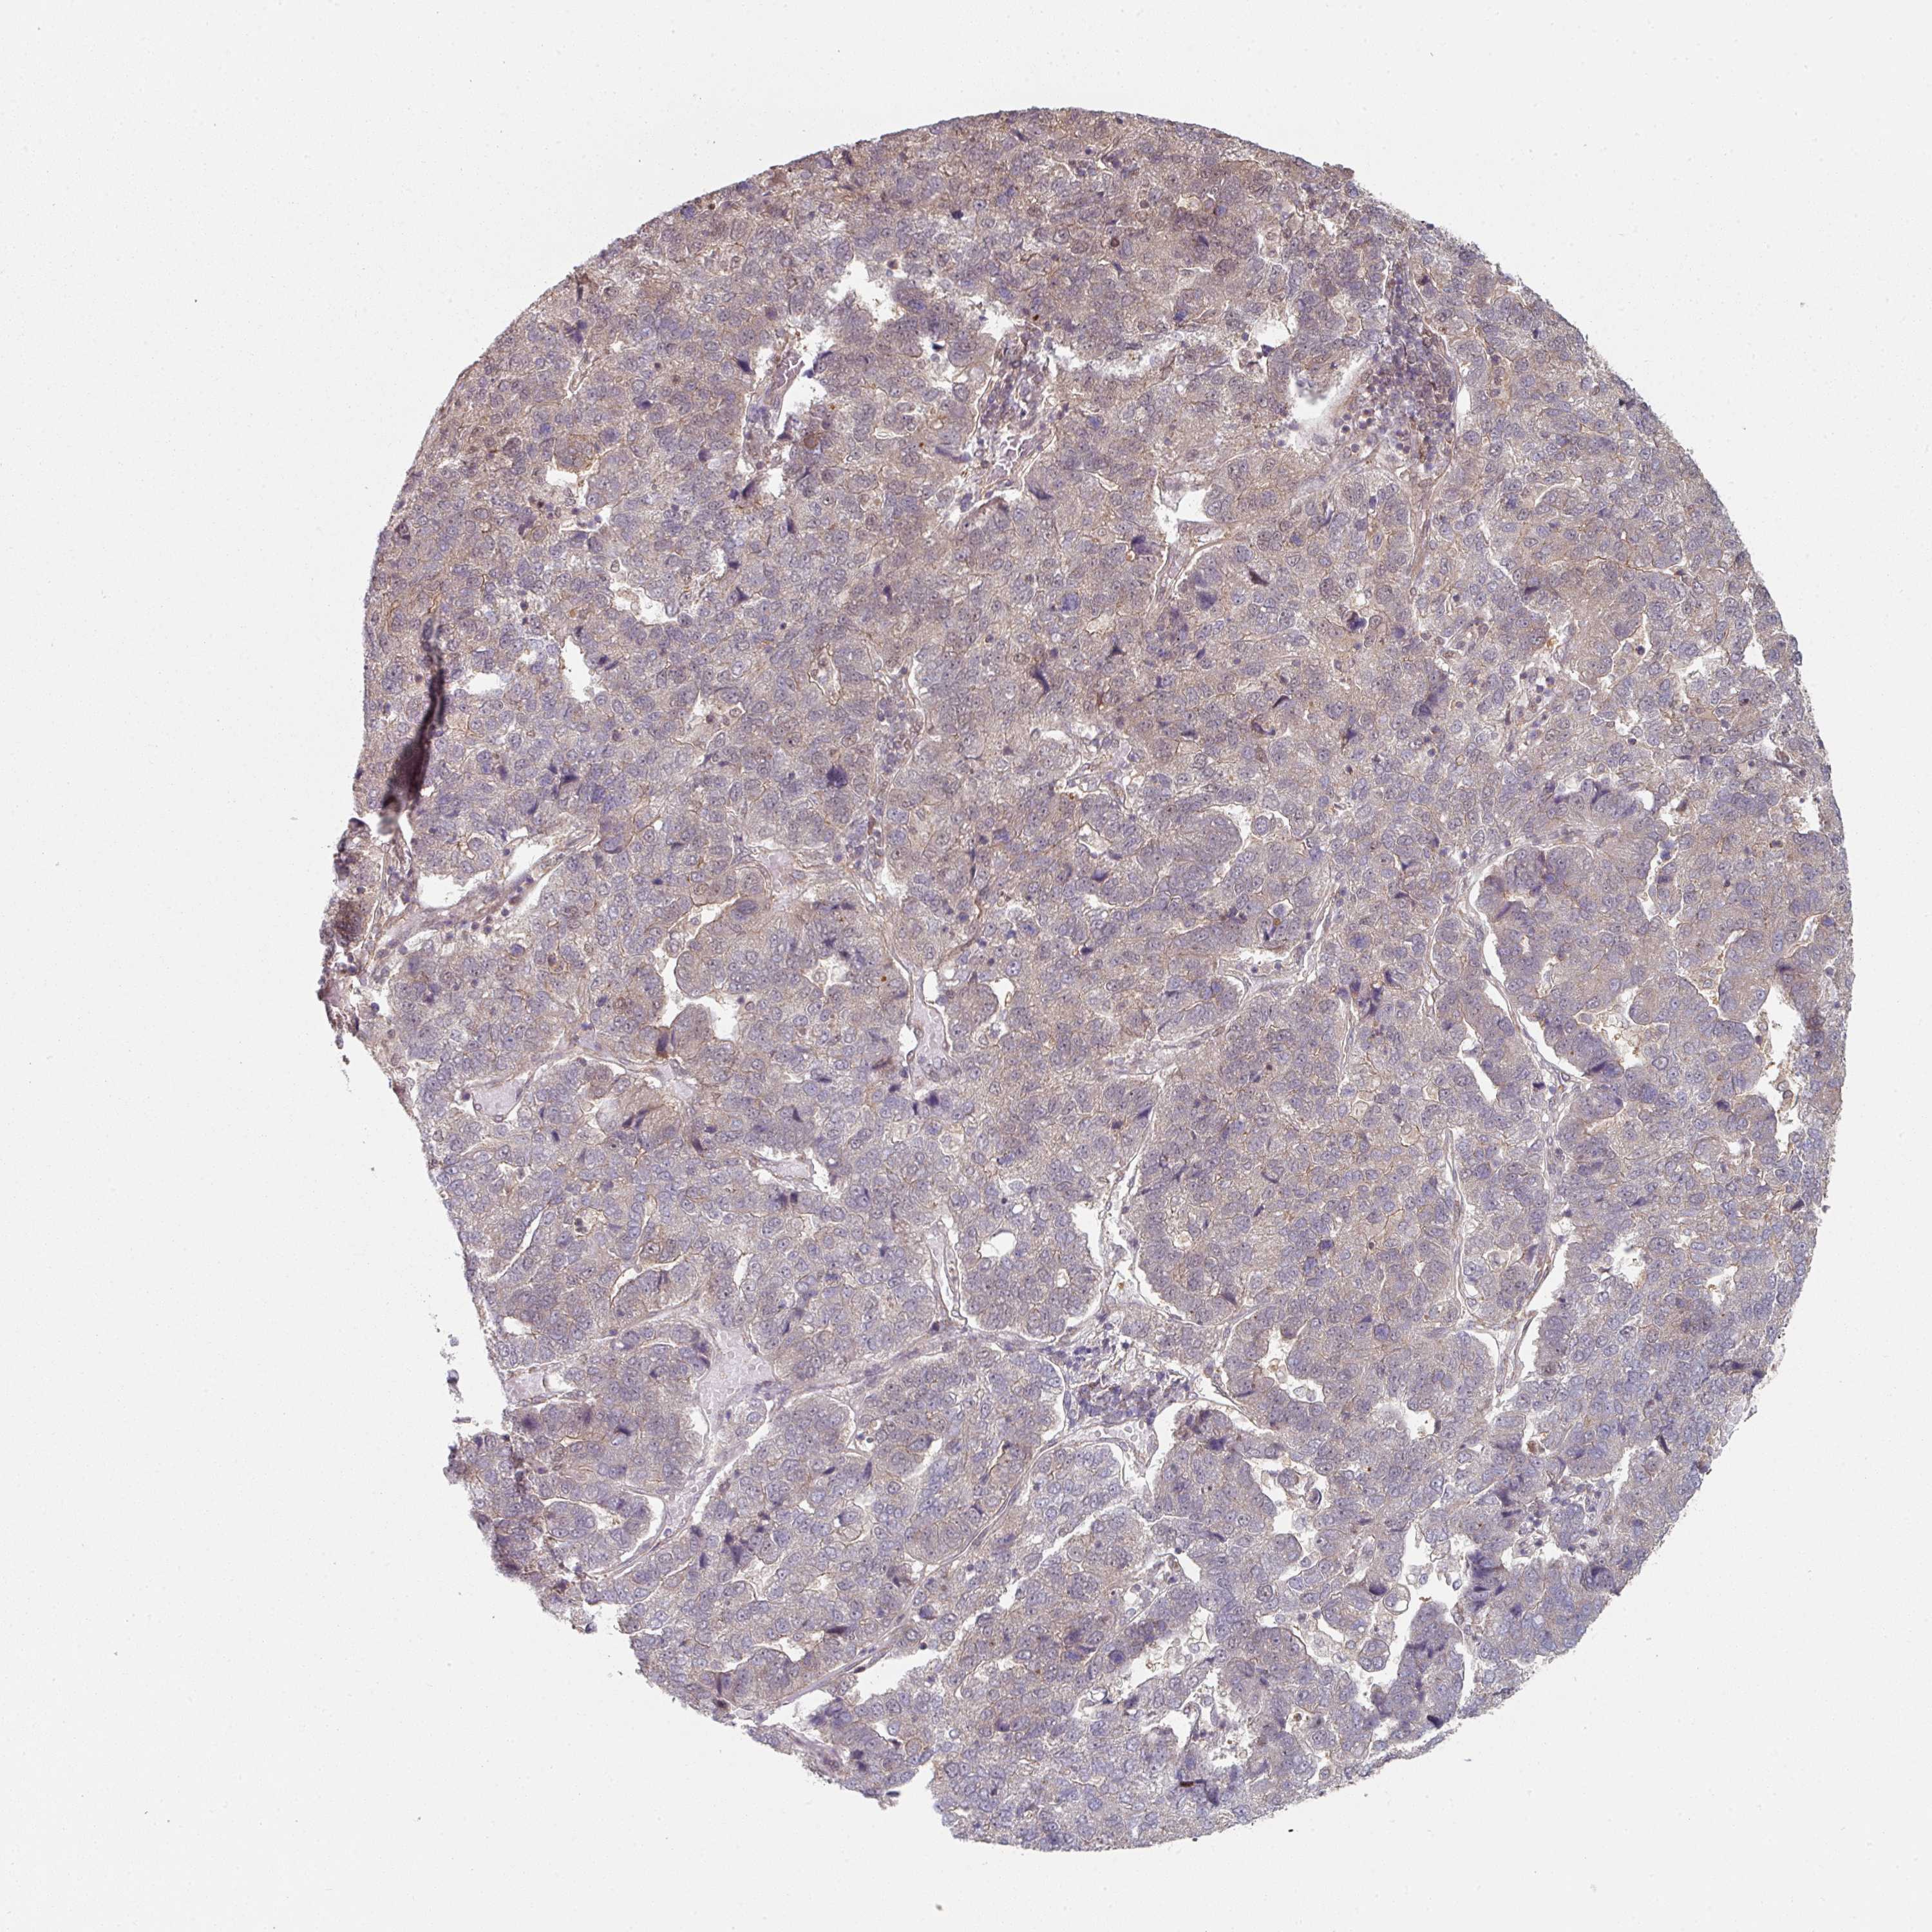

PANCREATIC CANCER - Protein expressioni

A mouse-over function shows sample information and annotation data. Click on an image to view it in a full screen mode. Samples can be filtered based on level of antibody staining by selecting one or several of the following categories: high, medium, low and not detected. The assay and annotation is described here.

Note that samples used for immunohistochemistry by the Human Protein Atlas do not correspond to samples in the TCGA dataset.

Antibody stainingi

Antibody staining in the annotated cell types in the current human tissue is reported as not detected, low, medium, or high, based on conventional immunohistochemistry profiling in selected tissues. This score is based on the combination of the staining intensity and fraction of stained cells.

Each image is clickable and will lead to virtual microscopy that enables deeper exploration of all samples and also displays staining intensity scores, fraction scores and subcellular localization as well as patient and tissue information for each sample.

Antibody HPA054382

Staining

High

Medium

Low

Not detected

Intensity

Strong

Moderate

Weak

Negative

Quantity

>75%

75%-25%

<25%

None

Location

Nuclear

Cytoplasmic/membranous

Cytoplasmic/membranous,nuclear

Adenocarcinoma, NOS